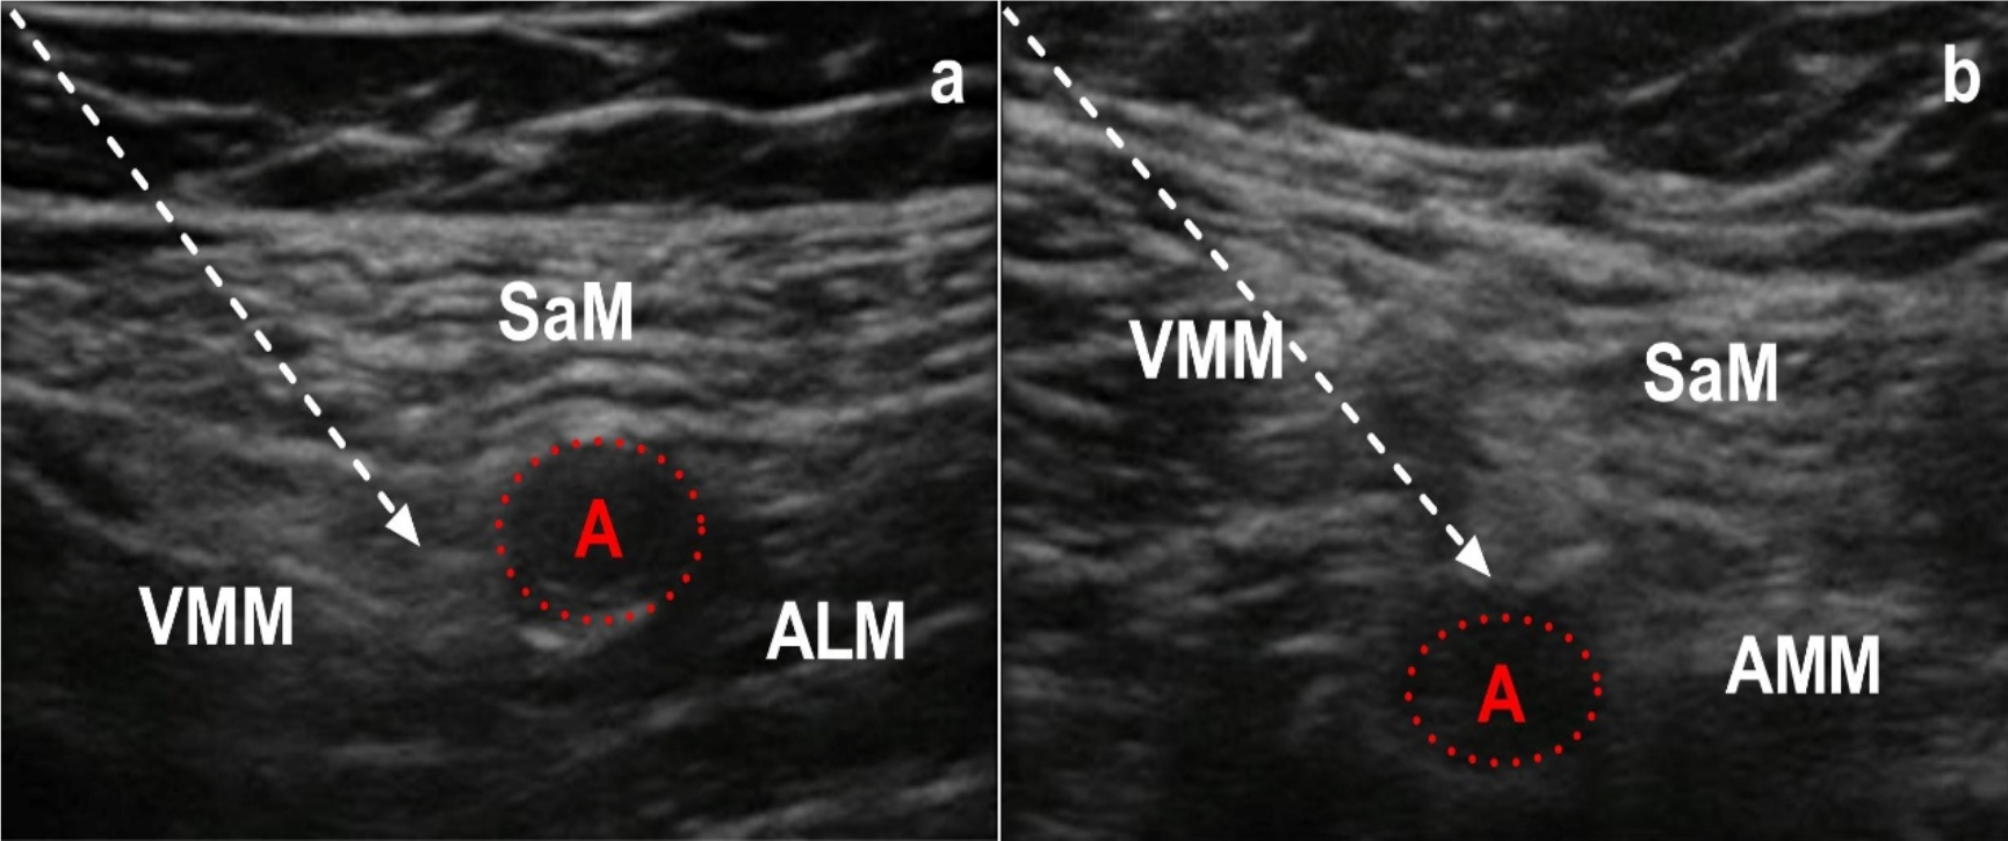

Adductor canal block (a) and popliteal plexus block (b). S sartorius muscle, VM vastus medialis muscle, AL adductor longus muscle, A femoral artery, and white arrow indicates needle of nerve block.